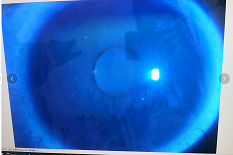

圓錐角膜要做那種治療比較好

瘢痕期:角膜急性角膜水腫、混濁,消退后基質(zhì)層殘留瘢痕。